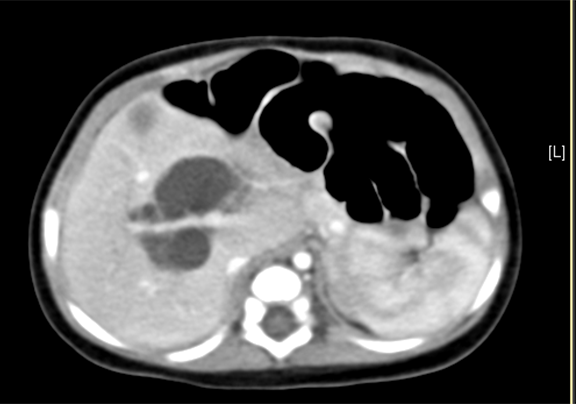

上腹部增强CT:先天性胆管扩张症(胆总管囊肿)可能性大。

术前CT检查:

动脉期

静脉期

平衡期